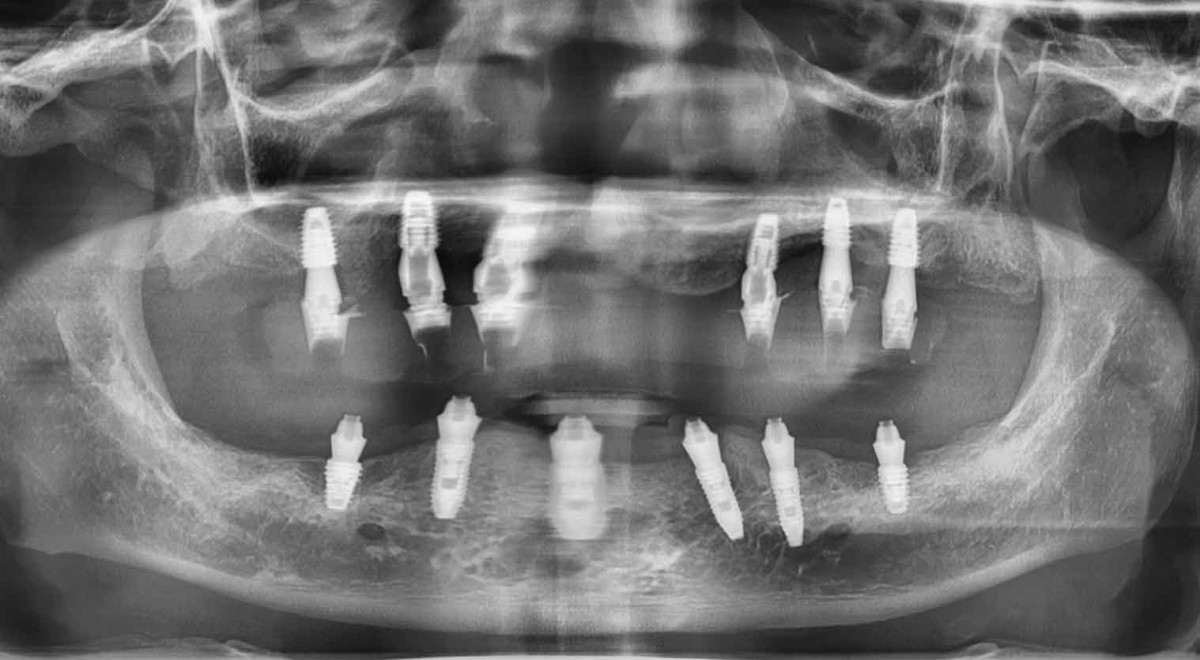

#무치악임플란트는 전체적인 치료계획으로 꼼꼼하고 확실하게 진행할 수 있어야 합니다.

#전체임플란트는 심한 #충치나 #치주질환 및 사고의 이유로 모든 치아를 상실한 경우이고

본인의 치아처럼 회복하기 위해서는 악당 12개에서 20개 이상의 임플란트를 식립하는 난이도가 높은 큰 치료입니다.

그리고 환자에게 분답 스럽지 않게 최소한의 개수로 최대한의 효과를 내느냐 입니다.

#서울라이프치과에서는 #강서구치과 최초 디지털 #풀아치임플란트 도입하여

최소 4~6개 최소의 개수의 임플란트로 전체 치아가 완성됩니다.